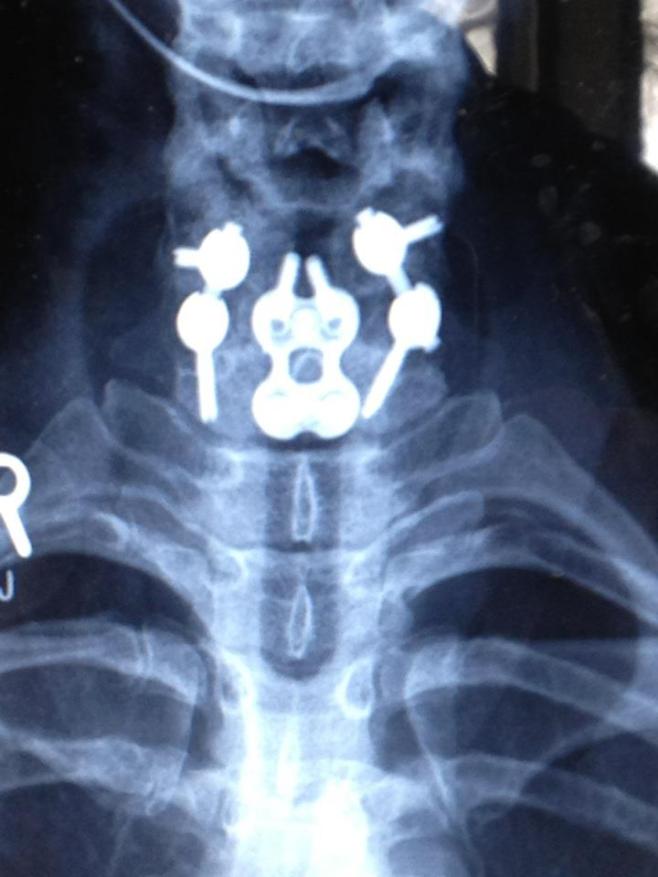

EMS was called out of Magrath, and our family friend, Karen Alston, and several others were with her. They cut me out of the car, put me in a Cspine collar and on a spine board. They took me right back to ED in Lethbridge and called my parents. I have absolutely no memory of any of this, but was talking and moving all extremities. Karen told my mom that I kept saying ‘what did I do wrong?’ and in fact continued to say that while in ED, perseverating, with obvious concussion symptoms. My family met me after going for imaging. Initially it was thought that I had suffered bumps, bruises, a bad concussion, and would likely take a few days to recover. My dad and mom were in emerg with me and apparently after the docs had left, I had asked my dad for a priesthood blessing. He told me afterwords that I was blessed that I would regain my health following this, and that the doctors involved in my care would be blessed as well. At that point, it was thought that I would likely be going home that night. However, the Xrays returned showing burst fractures of C6, C7, and possible fracture of C1 of the cervical spine. These types of fractures usually result in death or paralysis from the neck down. I was immediately prepped to head up to Calgary for Neuro assessment. STARS was called, but it was thought that would could actually get to Calgary faster driving than flying as prep time was significantly less driving at this point. They basically rolled me out to the ambulance in the collar and on the board. My mom came with me, and Dad went home to get everything ready to spend time in Calgary.

I remember Dr Duplessis, the neurosurgeon on call, explaining to me what had happened. Strangely, although I knew exactly what these types of fractures implicated, I had this overwhelming sense of warmth, calmness, and hope. I did not feel frightened, I did not feel worried, but I do not think that my brain was really going beyond that very moment in time. The pain medications were strong, but I remember hearing him very clearly and thinking that there was no way that I would not recover from this. I know that my family was there with me, and I know that the neuro team had decided to put me in a halo for at least the next several hours to determine if this would allow for decompression of the spine. From what I was told, with the initial impact, my the muscles of my neck immediately tightened around the area that was fractured which prevented movement of the fractured bone, but also would make it difficult to deal with in surgery.

I foggily remember them cutting my hair, and injecting the anesthetic where the screws were about to go in my forehead and over the occipital region. Gratefully, with the help of good pain meds, I do not remember the screws actually being placed, or apparently the crunching sound that followed as they tried to place traction on my spine. Unfortunately there was no movement of the bones, so they removed the halo and hoped that decompression with happen with general anesthetic.